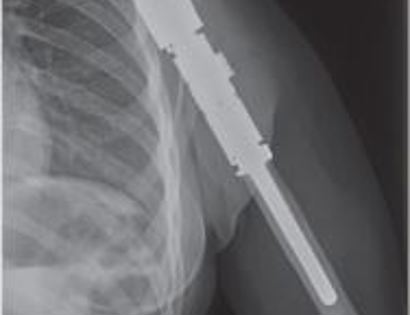

This is an x-ray image of an endoprosthesis in the arm. The prosthesis is made to match the length of the original bone and soft tissue reconstruction covers the prosthesis to maximize functioning postoperatively.